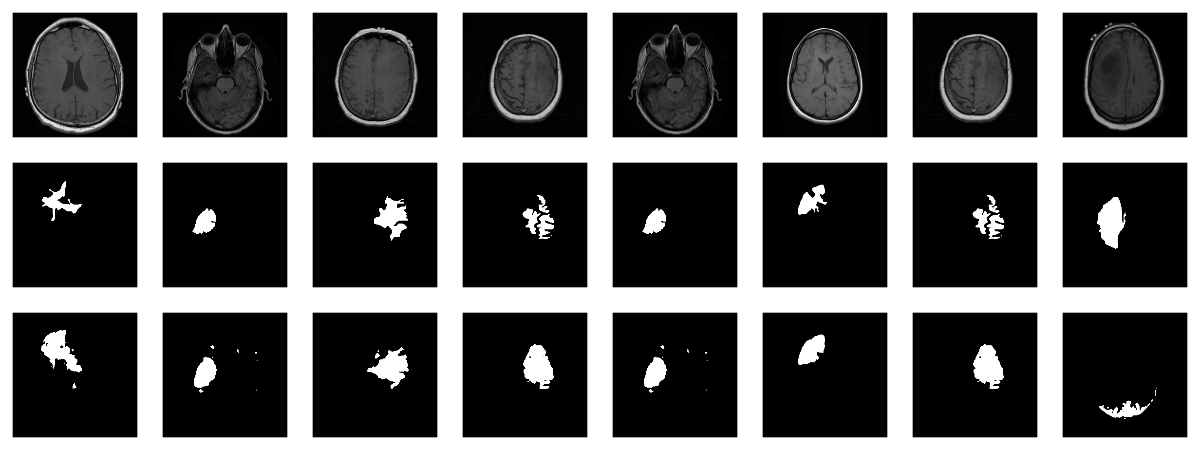

With torch, it is straightforward to inspect what happens when you change augmentation-related parameters. We just pick a pair from the validation set, which has not had any augmentation applied as yet, and call valid_ds$<augmentation_func()> directly. Just for fun, let’s use more “extreme” parameters here than we do in actual training. (Actual training uses the settings from Mateusz’ GitHub repository, which we assume have been carefully chosen for optimal performance.1)

plot_grid(plotlist = imgs, nrow = 4)